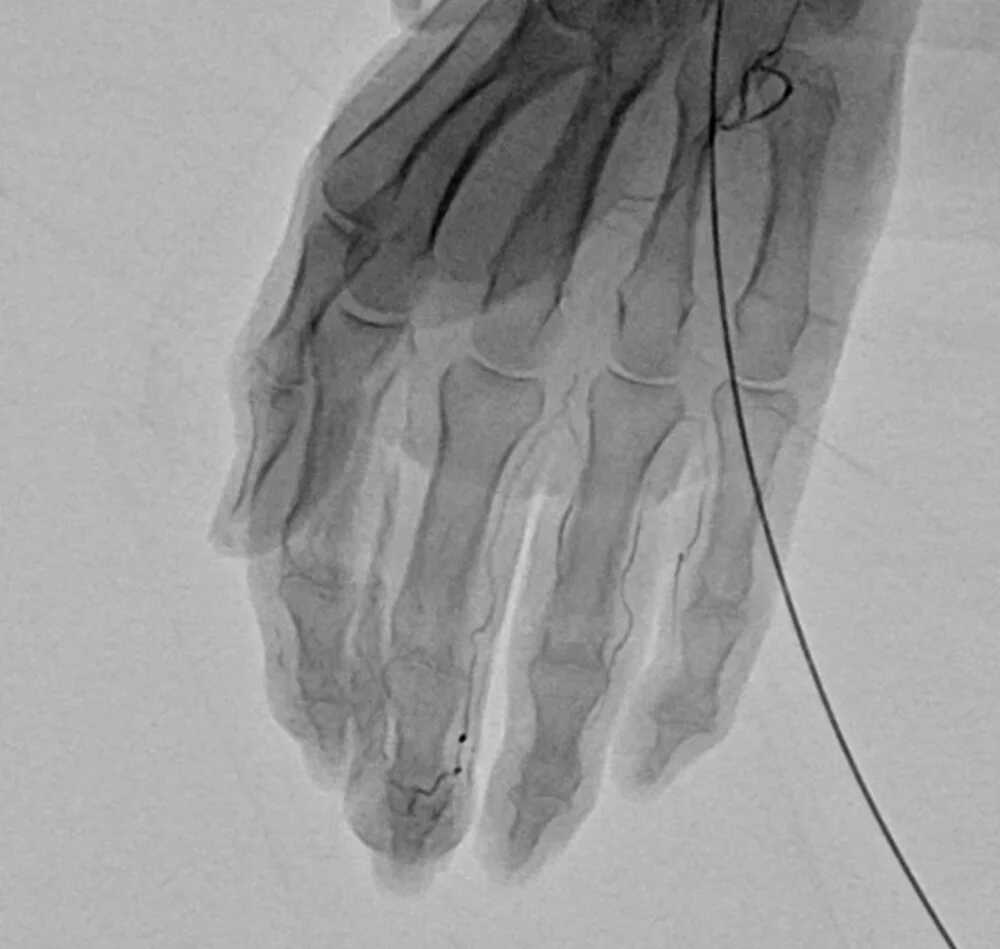

動注治療(モヤモヤ血管治療)とは?

動注治療とはモヤモヤ血管治療とも言う自費治療です

炎症部位より上流の動脈に抗生物質を注入し、モヤモヤ血管だけを塞栓(詰める)する事で痛みを軽減させる治療法です

モヤモヤ血管は細く流れが遅い為、特定の抗生物質で塞栓可能です

また血管構造も不完全なので、塞栓効果が持続します

常な血管は太く流れも速いので、血流を阻害する事は有りません

レントゲン撮影により骨等の変性の有無を確認します

血流の増強等をエコーを使用し確認します

- エコーで血管の位置を確認しながら、細い針を刺します